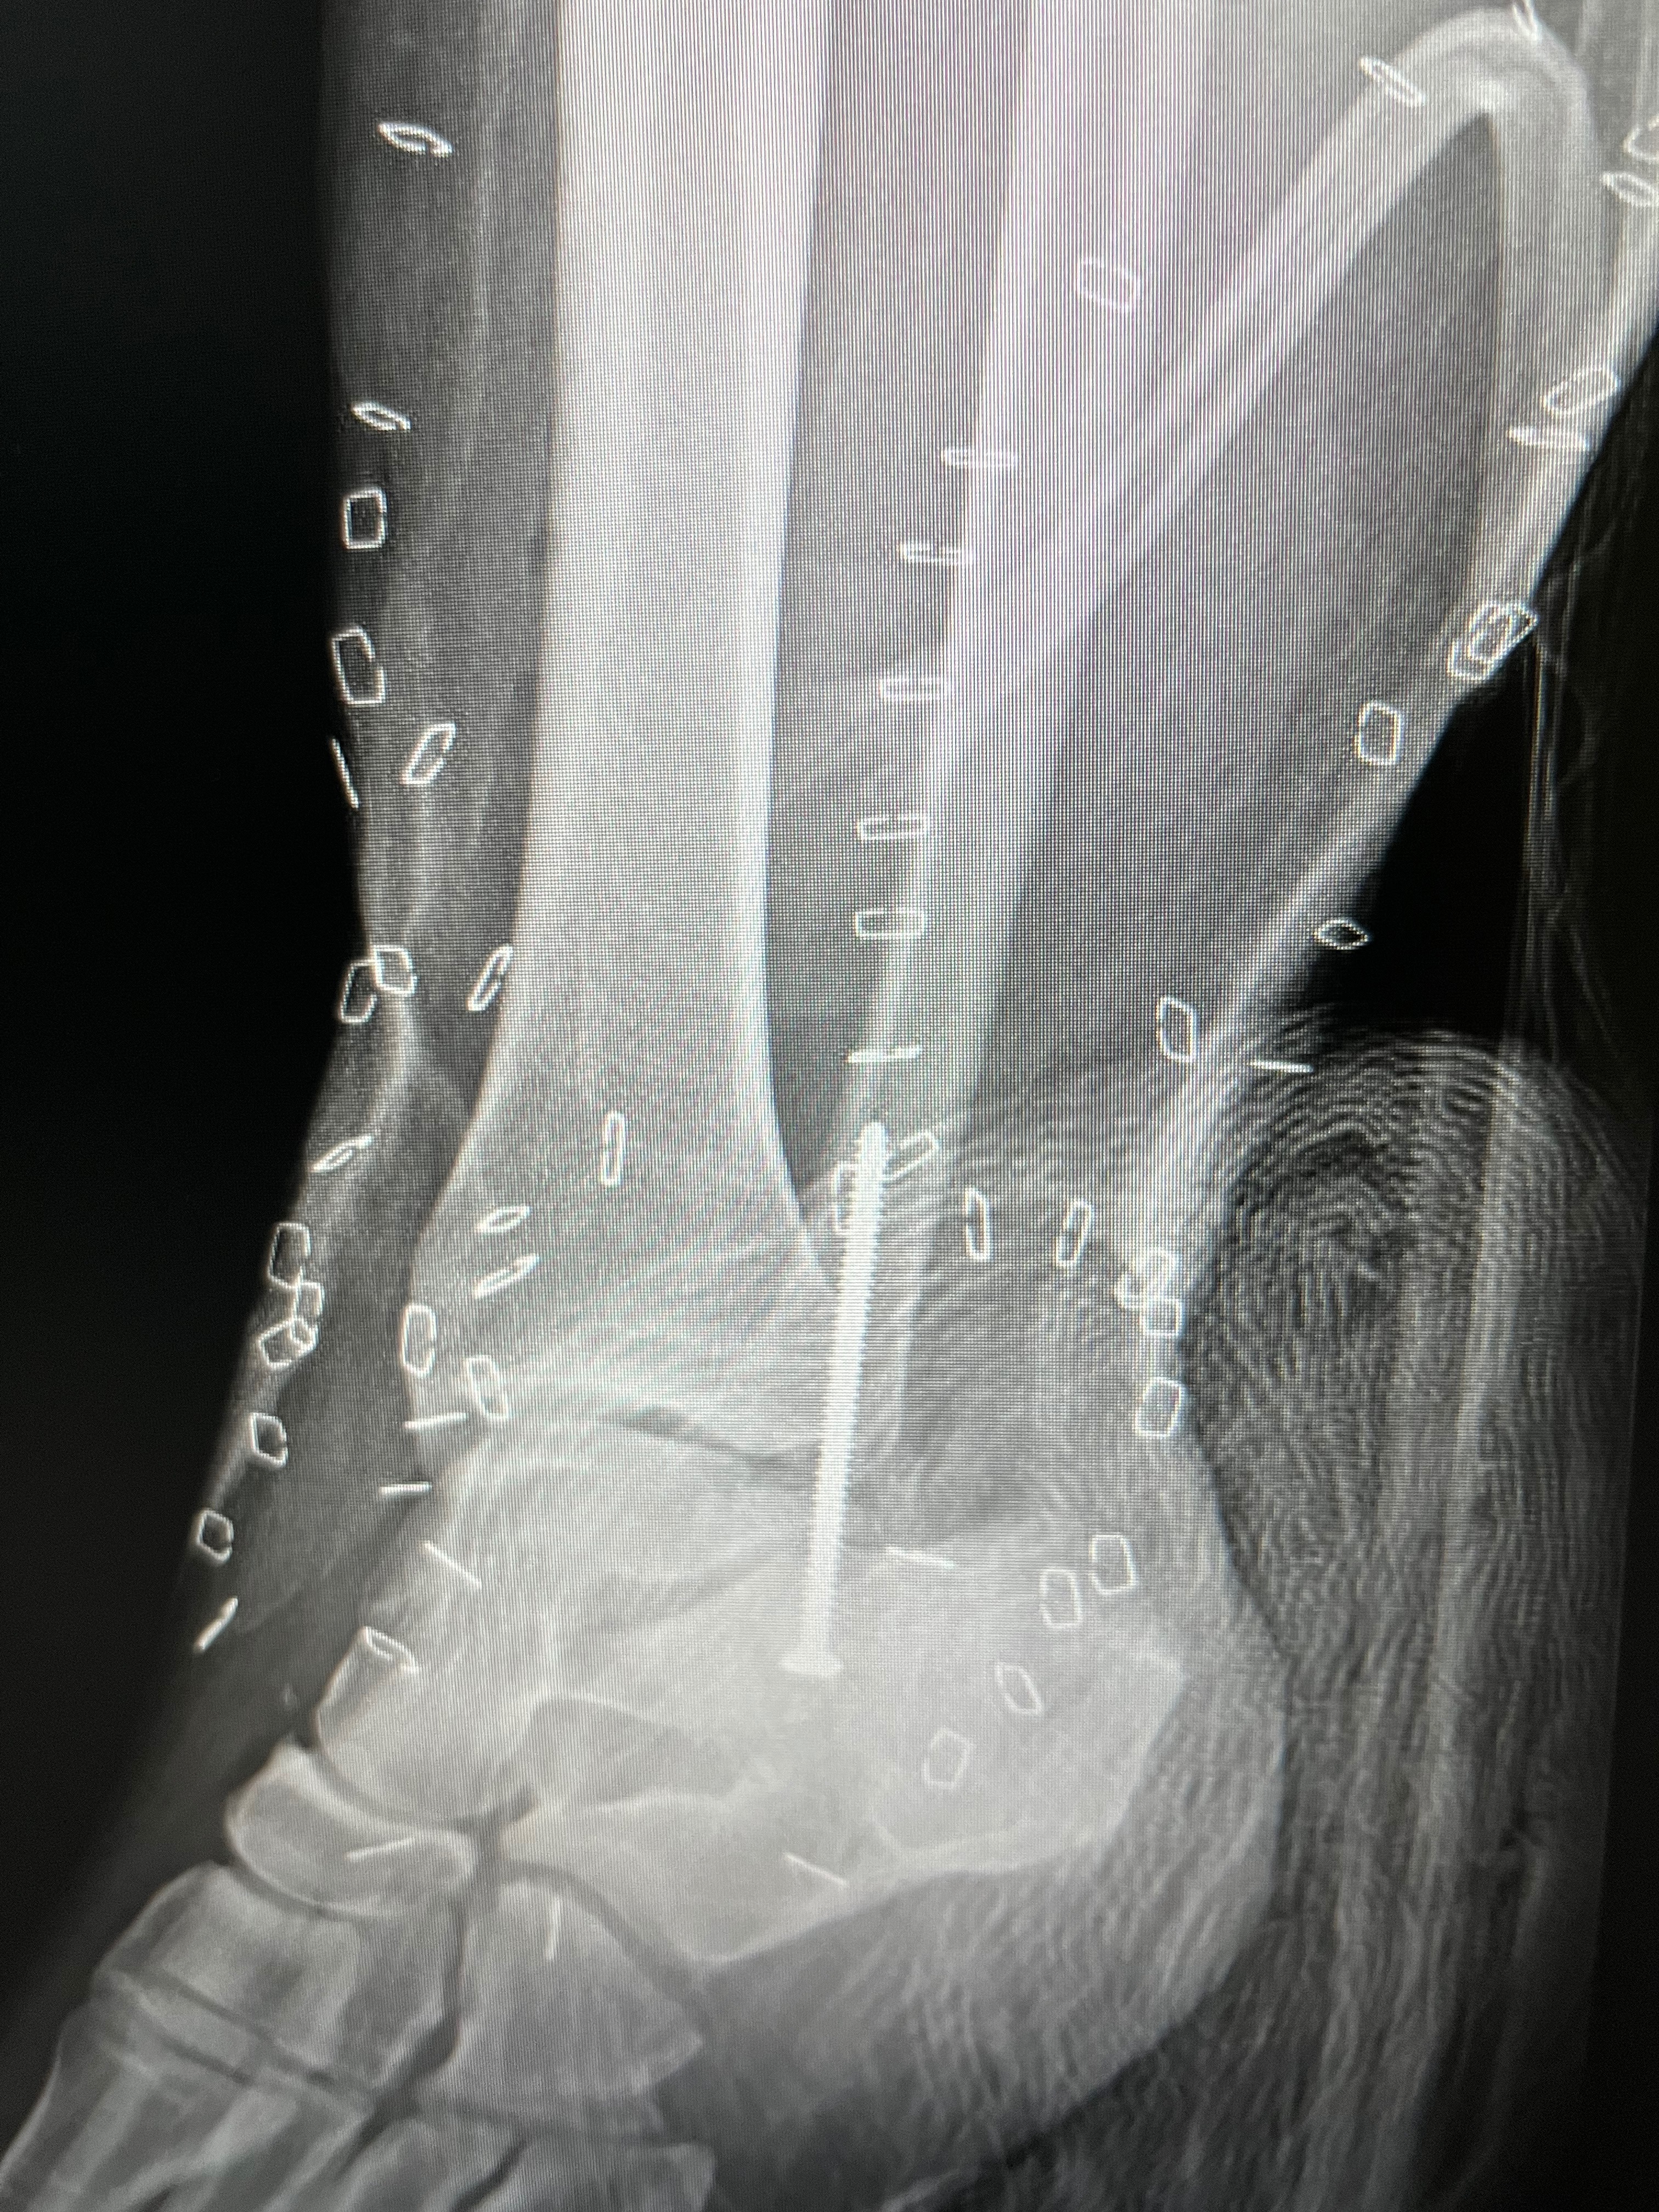

On Dec 9th at approximately 8am, my daughter was involved in a vehicle hit and run. She got out of her car on the Kemah bridge because she had a flat tire. The next thing she remembers is coming to about 40 feet from her car, a 2018 Red Jeep Renegade. Her phone and shoe were in the middle of the bridge. The car that hit her never stopped to render aid. She got up and remembers dragging her right leg to get her phone to call for help. As people were passing her and she was screaming, crying, and waving passing cars down for help, no one stopped to help her. Someone, however, did contact 911, letting them know there was a bleeding woman on the Kemah bridge. EMS showed up and debated life-flighting her to UTMB but chose to just rush her by EMS instead of waiting. She has a broken left foot, a fractured left knee, a broken left ankle, a broken right pelvic bone, 5 staples in her head, 3 spots fractured on her spine, and a contusion on her brain. She will lose the skin between her knee and ankle, needing skin grafts as healing happens. She is stable, but we have a long way to go. She has had 8 surgery's. She will be in the hospital through Christmas and possibly even New Year's. She has four beautiful girls and several family members praying for her. We ask that if you know anything about her accident, please reach out to Detective McGee with the Seabrook Police Department. Please continue to pray for Kristie and her girls and our family.